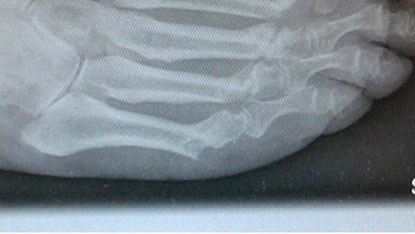

Lagerung des Patientenfußes auf dem Röntgendetektor des Bildversärkers.

Abbildung 1

Abwaschen und steriles Abdecken des Fußes und Sprung­gelenkes. Die Operation erfolgt normalerweise ohne Blut­sperre. Der Patientenfuß ragt über das distale Ende des Op Tisches hinaus. Der Unterschenkel wird auf einem Beinhalter gelagert. Der Fuß selber wird auf dem Röntgen­detektor des am Fußende stehenden Bildwandlers aufgesetzt. Der Bild­wandler wird zum Patienten geneigt (Abb.1).